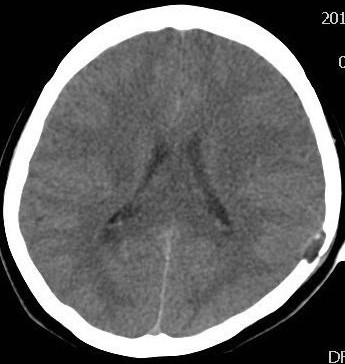

1.X线/CT:显示溶骨性破坏(边界清晰,局限性颅骨缺损,缺损边缘不规则呈“虫蚀样”改变,颅骨内外板受破坏,在病变组织内可见条索小骨影,病变周围可见软组织块影征象)。